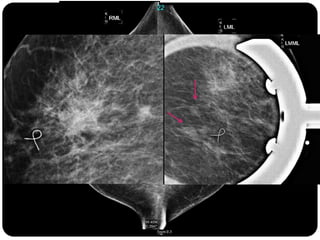

Paciente femenina de 66 años con historia clínica de 1er gesta antes de los 30 años y antecedentes de lactancia positiva, presenta una lesión palpable en la mama derecha. Los estudios radiológicos indican un diagnóstico de bi-rads 5, con biopsias revelando adenocarcinoma lobulillar infiltrante en la glándula mamaria derecha y adenocarcinoma ductal in situ en la izquierda. El caso fue evaluado por las doctoras Jacqueline Preciado Vargas y Beatriz E. González Ulloa.